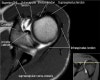

- Sagittal section

1) T1WI : Rotator cuff muscle size, fat infiltration, Biceps tendinosis

2) T2WI : Rotator cuff insertion, edema, Rotator cuff partial or full thickness tear, Bursa fluid collection, Acromial type ,Glenoid fossa, Superior, middle, inferior GHL

근육 안에 tendon이 들어있다

원외부에서 SST와 IST가 겹침